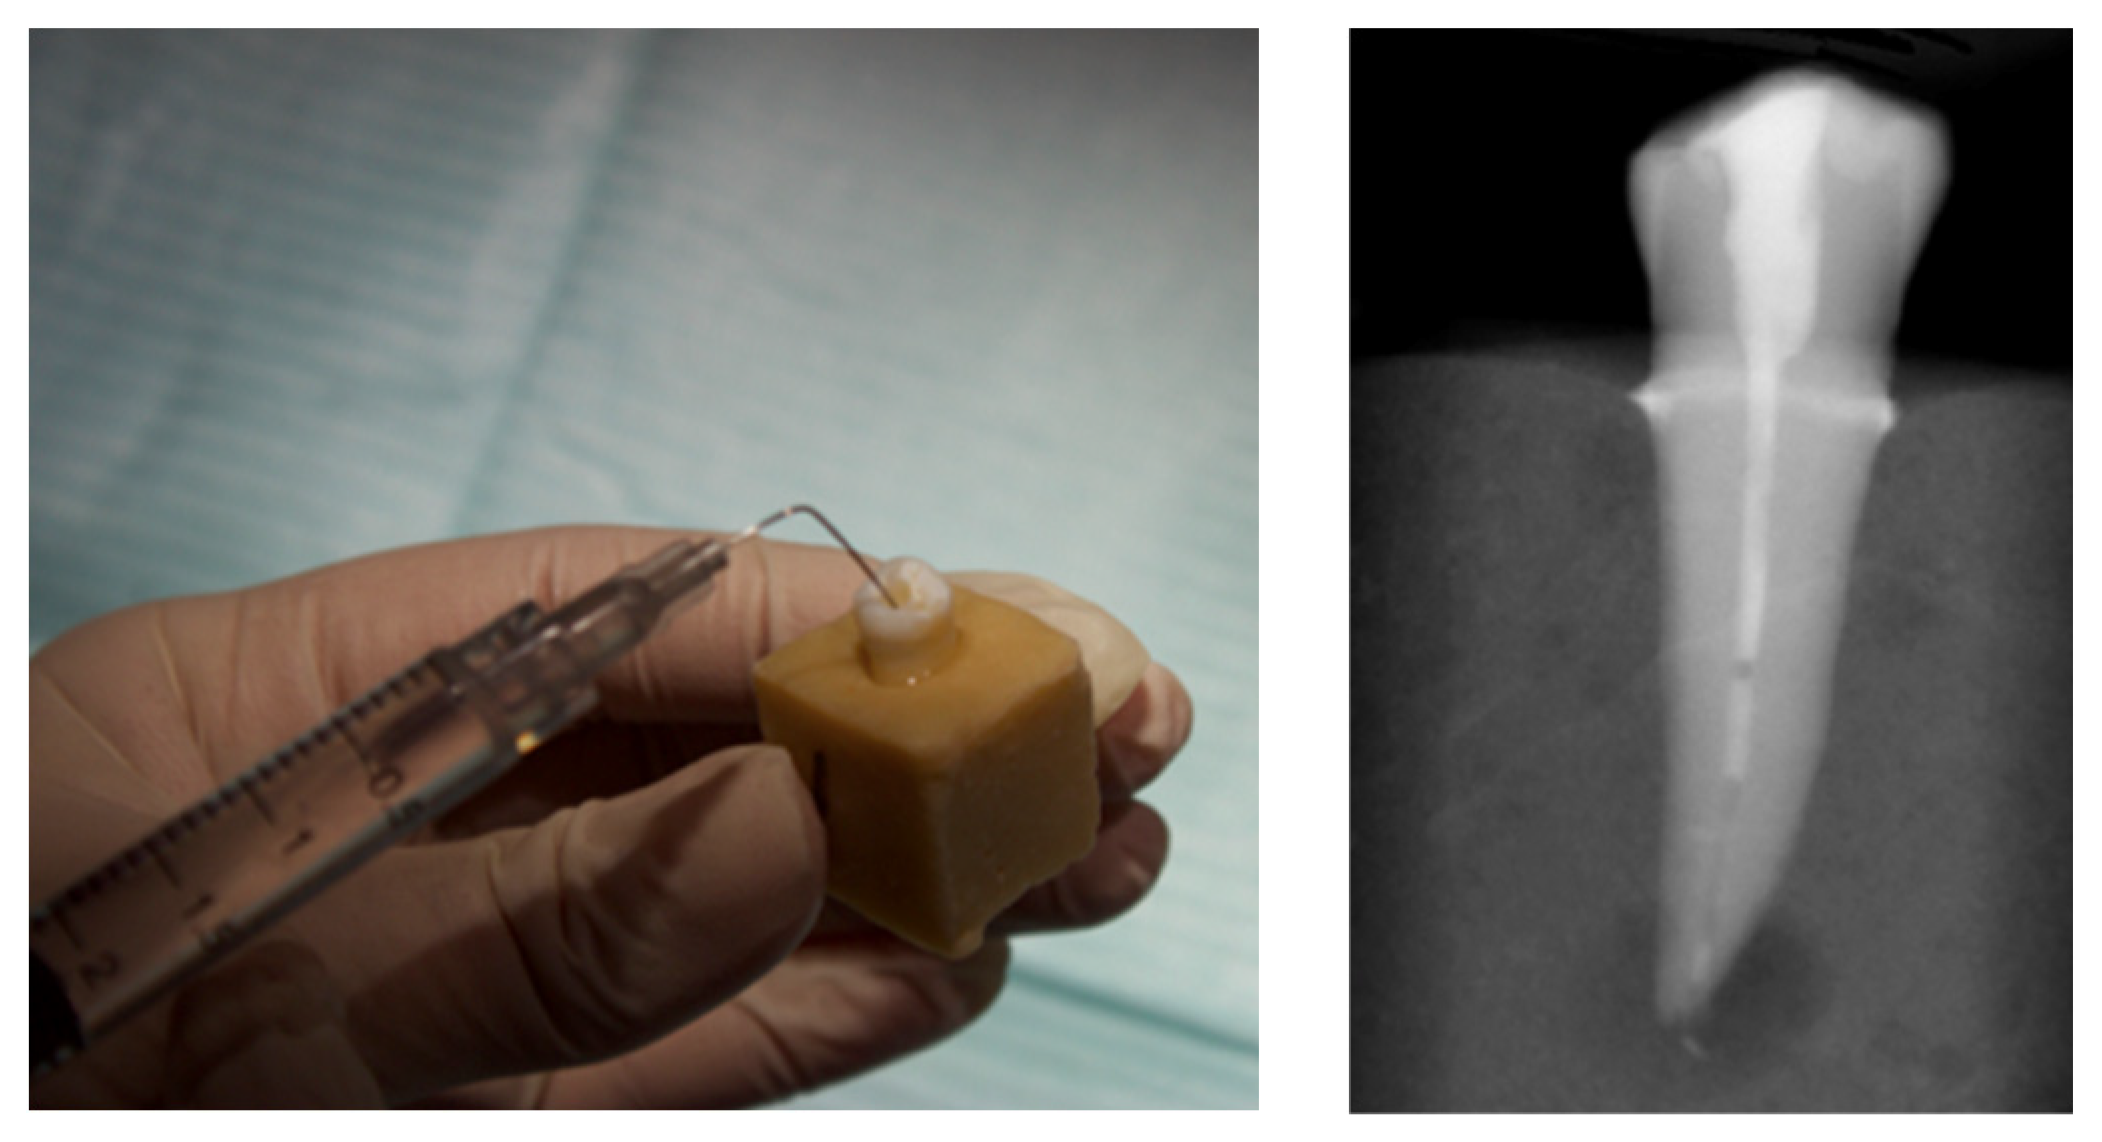

Enjoy Minimally Invasive Endodontics with Laser Activated Irrigation

Minimally Invasive Endodontics with Laser Activated Irrigation Final Endodontic Irrigation With 70 Ethanol The aim of this study was to evaluate the efficacy of different lengths of time of passive ultrasonic irrigation (pui) in removing calcium. Irrigation with 70% ethanol presented a significantly higher percentage of clean root canal walls and a higher depth of clean dentinal tubules. Irrigation with 70% ethanol presented a significantly higher percentage of clean root canal walls and. Final Endodontic Irrigation With 70 Ethanol.

Enjoy Minimally Invasive Endodontics with Laser Activated Irrigation Final Endodontic Irrigation With 70 Ethanol Irrigation with 70% ethanol presented a significantly higher percentage of clean root canal walls and a higher depth of clean dentinal tubules when. Results irrigation with 70% ethanol presented a significantly higher percentage of clean root canal walls and a higher depth of clean. Irrigation with 70% ethanol presented a significantly higher percentage of clean root canal walls and a. Final Endodontic Irrigation With 70 Ethanol.